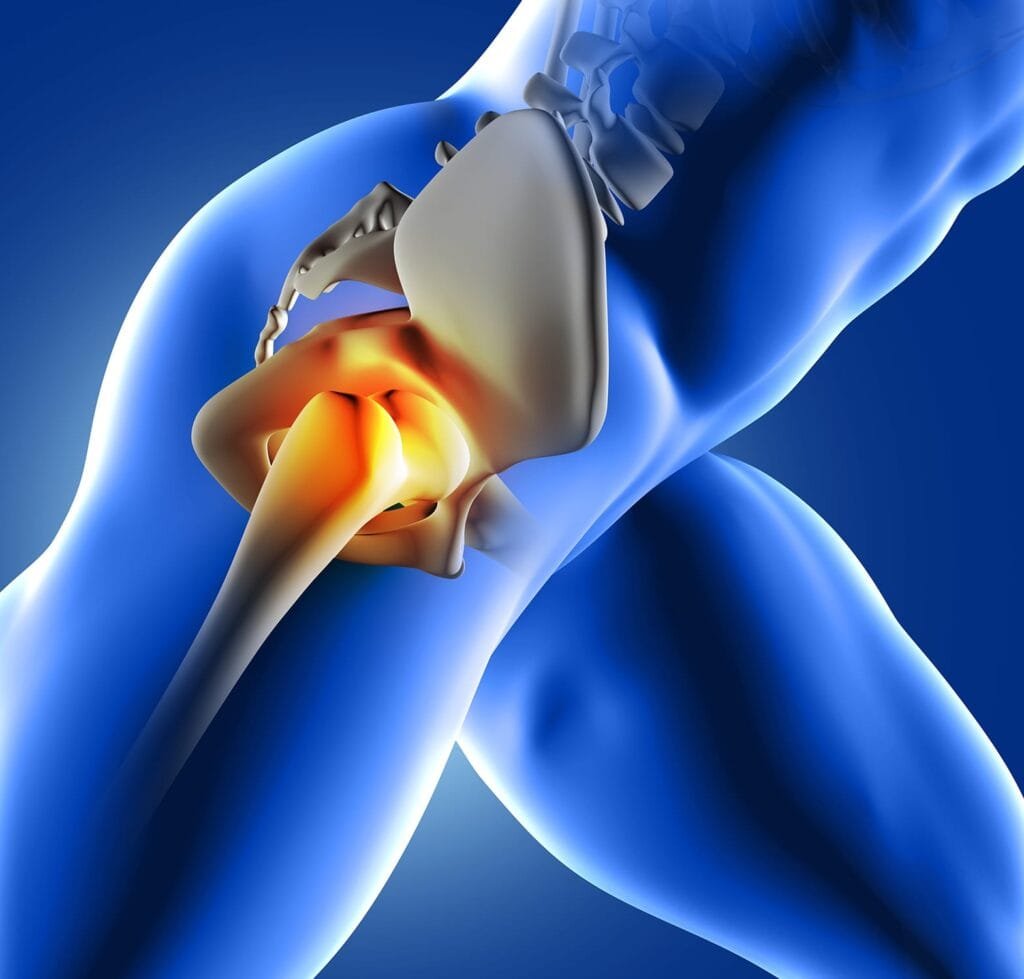

Síndrome do Impacto Femoroacetabular (SIFA)

Vídeo explicativo desenvolvido pelo Prof. Frederico Meirelles explicando o que é a Síndrome do Impacto Femoroacetabular. A síndrome do impacto do quadril, também conhecida como síndrome do impacto femoroacetabular (SIFA), é uma condição na qual há contato anormal entre a cabeça femoral e o acetábulo da articulação do quadril. Isso pode causar dor, rigidez e redução da amplitude de movimento no quadril. Geralmente é causada por anormalidades estruturais nos ossos do quadril, como uma protuberância na cabeça do fêmur ou um acetábulo raso. Também pode ser causada por desequilíbrios musculares ou lesões por uso excessivo. As opções de tratamento para a síndrome do impacto do quadril podem incluir fisioterapia, medicamentos e, em casos graves, cirurgia. Se você tem Síndrome do Impacto Femoroacetabular procure um Fisioterapeuta para um tratamento adequado.